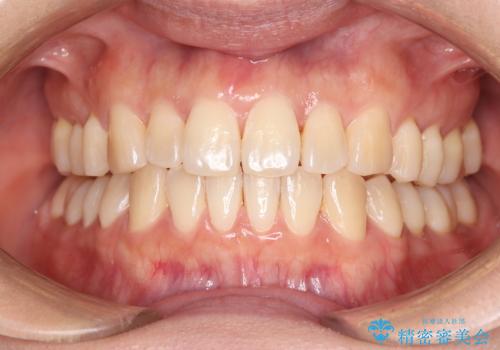

前歯の隙間とへこみが舌で触ると気になる|矯正治療は絶対にしたくない|抜歯即時インプラント+オールセラミッククラウンで審美修復

[ セラミック治療 ] 前歯の見た目を改善したい